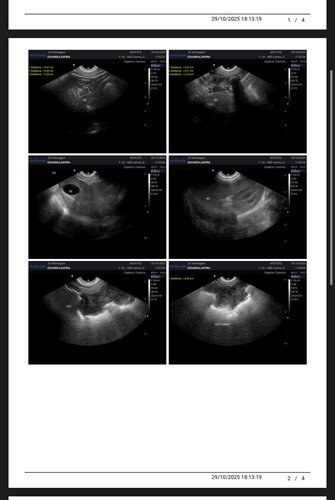

Alguns meses atrás realizamos exames e biópsia que teve como resultado hemangioma, um tumor benigno que poderia virar um tumor maligno chamado emangiossarcoma. Como são vários nódulos pelo corpo dela, existia chance de algum deles já ser maligno. Então nossa saída era fazer outros exames para poder começar uma eletroquímio, porém na ultrassom encontramos uma neoplasia de 14cm na parede do estômago, cisto no ovário esquerdo e pancreatite.

Já fizemos a gastrectomia para biópsia e castração, para agora acompanhar com ultrassom. Para um cachorro de grande porte e uma cirurgia delicada, o custo que já era alto ficou ainda maior. Felizmente está tudo correndo bem, ela está ótima para alguém que operou. Hoje, clinicamente ela está bem e não apresenta nenhum sintoma, então é o melhor momento para tratar a cuidar dela. Estamos com um veterinário de muita confiança para observar cada mudança com ela e aplicar vitaminas que são importantes para o imunológico dela. Mas ainda temos que terminar de pagar os custos dessa primeira primeira parte que passamos. Não pretendemos atingir metas, mas qualquer ajuda será recebida com muita gratidão! Se começarmos temos que ir até o final, pelo bem e carinho que temos por ela. Toda ajuda é bem vinda!